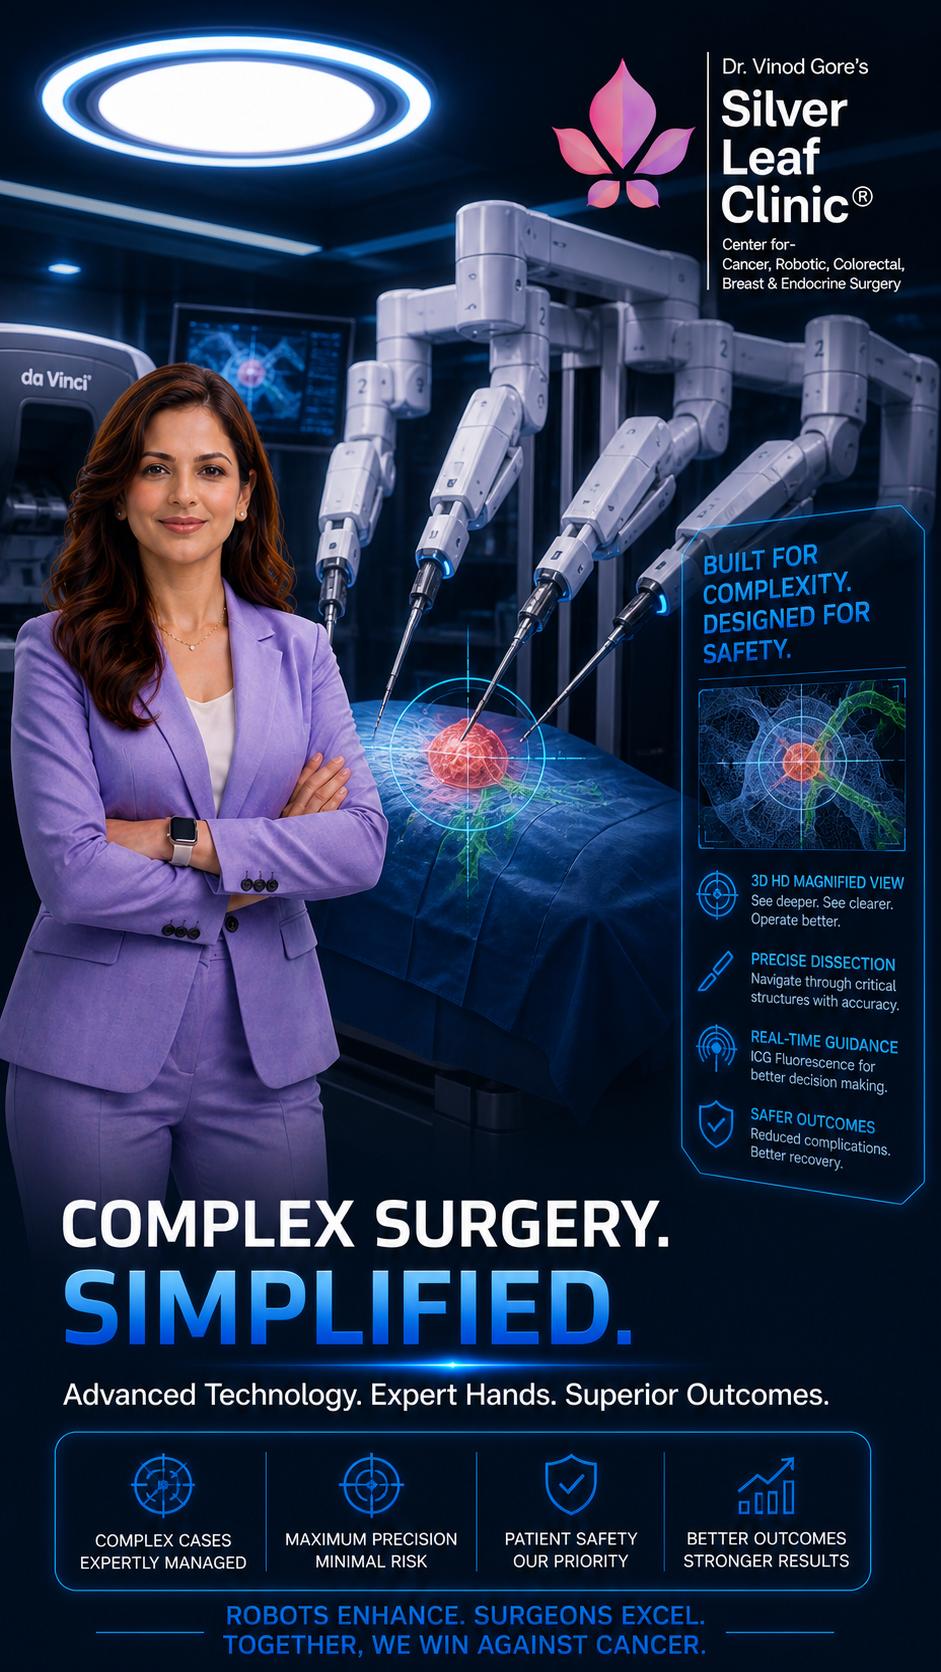

Don't Miss the Signs. Trust Robotic Precision

Take step confidently into a healthier future

Prioritize your well-being today